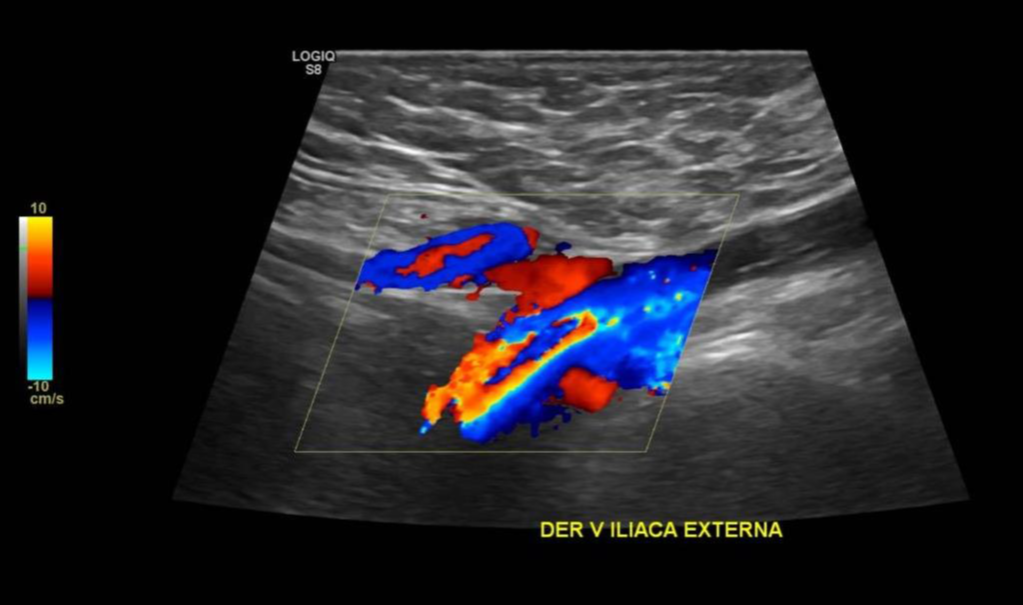

• Desde la VFC se visualiza contenido ecogénico interno, no compresible y sin señal al Doppler Color sugerente de Trombo que se extiende por toda la cara posterior del muslo comprometiendo a la Vena Femoral Profunda. Vena Femoral Superficial permeable.

Hallazgos: Piel y tejido subcutáneo sin alteraciones. Material ecogénico endoluminal en vena femoral común, vena femoral superficial y profunda, con ausencia de flujo y compresibilidad, compatible con trombosis venosa profunda en evolución. Planos musculares de aspecto ecográfico conservado, sin evidencias de desgarros fibrilares. Engrosamiento disminución de ecogenicidad inserción proximal de los isquiotibiales, sin desgarros. No se observan lesiones nodulares ni quísticas. Contornos óseos visualizables regulares. Impresión

Diagnóstico: Hallazgos compatibles con trombosis venosa profunda de vena femoral común, vena femoral superficial y profunda. Es indispensable evaluación clínica de urgencia. Entesitis proximal de los isquiotibiales.